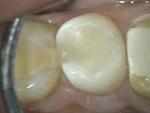

| Рис. 69-70 Корневые каналы 1.5 зуба обтурированы в технике вертикальной конденсации горячей гуттаперчи по Шильдеру; выполнена пескоструйная обработка полости зуба | |||

| Рис. 71 Полость 1.5 зуба восстановлена композитом двойного отверждения (культевый материал – для дентина); эмаль 1.5 зуба восстановлена эмалевым гелиокомпозитным материалом Filtek Supreme |

| Рис. 72-73 Готовая прямая реставрация 1.5 зуба |